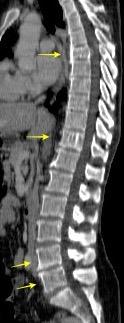

Líneas paraespinales formando un “paréntesis” por encima del diafragma. El signo señala el origen “intratorácico” de la lesión.

Conrad A et al. Pott’s disease associated with large and multiple abscesses in a 30-year-old migrant from Chad. BMJ Case Rep 2018

(lesiones toracoabdominales) La divergencia de las líneas paraespinales apunta a lesión toracoabdominal, que desde el tórax desciende y penetra en el abdomen.

Signo del “iceberg” positivo en Tb vertebral

Afectación por vía hematógena. Región dorsolumbar más frecuente. Afectación inicial: irregularidad de los platillos vertebrales, disminución del disco intervertebral con esclerosis ósea adyacente. Kim. Radiographics.2001